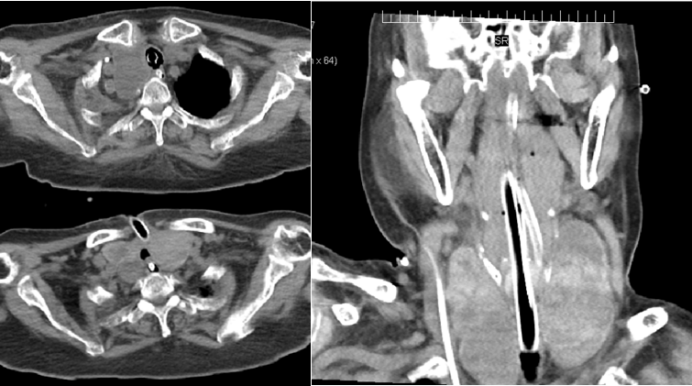

病例9:55岁男性患者,因“肺癌术后反复发热、咳嗽、咳痰伴呼吸困难1个月,加重3天”于2022年1月由某大型肿瘤医院转入。患者1个月前因肺鳞癌行右肺全切除术,术后出现右支气管残端胸腔瘘(图17),并发右侧脓胸、呼吸衰竭、脓毒性休克及重度低蛋白血症。支气管镜检查明确瘘口位置后,采用覆膜金属支架(封堵用L型)进行腔内封堵(图18),同时加强抗感染、营养支持及休克纠正,患者肺部感染逐渐控制,呼吸功能改善,最终好转出院,定期门诊随访

图片

17  右支气管残端胸腔瘘

18  覆膜金属支架封堵